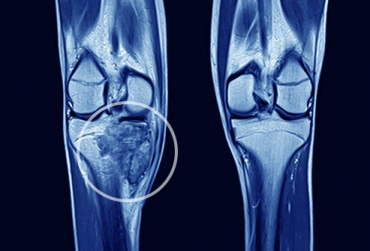

O médico esclareceu que o câncer ósseo, com exceção do sarcoma de Ewing, em geral não apresenta sintomas clínicos sistêmicos, como febre e perda de peso. A primeira avaliação no paciente pode ser feita por um clínico geral em um posto de saúde, orientou o presidente da ABOO. “Uma dor óssea que aparece e não tem explicação, que limita a atividade, não passa com o tempo, uma dor que persiste após duas semanas, merece investigação com radiografia”.

A radiografia feita com qualidade vai mostrar qual é a causa e, se for um câncer, vão aparecer as alterações do esqueleto. Uma observação mais cautelosa da radiografia já permite ao médico dizer que alguma coisa está errada e, então, encaminhar para um ortopedista ou, se já houver a confirmação de câncer, encaminhar a um centro de referência.

“A gente faz muita questão de que esse encaminhamento, depois de confirmada a suspeita de câncer ósseo, seja para um centro de referência, porque a biópsia, um dos primeiros procedimentos a serem feitos, tem que ser realizada com parcimônia. O ideal é que o cirurgião que vai fazer o tratamento definitivo faça também a biópsia. A gente reforça a ideia de que esse encaminhamento seja precoce”. Esses centros especializados têm mais presteza e rapidez para fazer os exames necessários, observou.